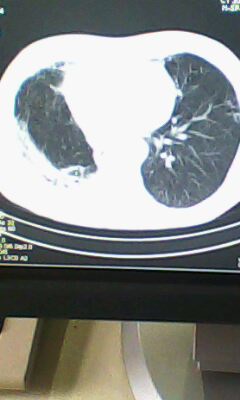

标题: CT25675:男 71 肺癌部分切除术后 3年 [打印本页]

标题: CT25675:男 71 肺癌部分切除术后 3年

两肺感染性病变,右侧肺膨胀不全,左侧上叶结节影及左侧颈部淋巴结肿大建议复查。

1)两肺感染性病变。2)右侧胸膜增厚。3)冠状动脉及主动脉钙化。

右肺癌切除术后。

右肺炎症,左肺炎症。

右侧胸膜肥厚。

两肺感染性病变\\右侧胸膜增厚

1.右肺符合肿瘤切除术后ct表现。

2.左肺炎症。

术后改变,双肺内纤维索条影考虑与放疗有关。